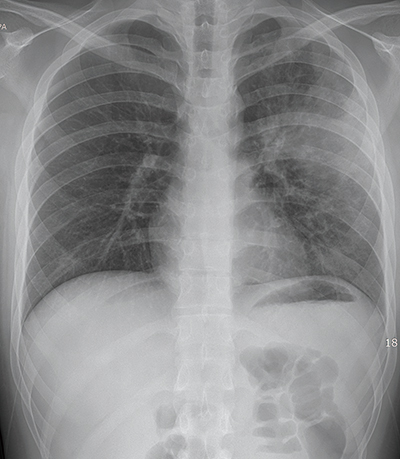

폐렴 치료 방법은 감염의 원인과 심각성에 따라 다르며, 대부분의 경우에는 항생제 치료가 필요합니다. 다음은 폐렴 치료 방법에 대한 상세한 설명입니다:

항생제 치료: 대부분의 폐렴은 세균 감염에 의한 것이므로, 선별적인 항생제 치료가 필요합니다. 의료진은 환자의 증상과 진단 결과를 바탕으로 적절한 항생제를 처방합니다.

대부분의 폐렴은 세균 감염에 의한 것이므로, 선별적인 항생제 치료가 필요합니다. 의료진은 환자의 증상과 진단 결과를 바탕으로 적절한 항생제를 처방합니다. 항바이러스제 치료: 바이러스 감염으로 인한 폐렴의 경우 항바이러스제 치료가 필요할 수 있습니다. 예를 들어 인플루엔자 바이러스에 의한 폐렴은 항바이러스제 치료를 통해 치료할 수 있습니다.

바이러스 감염으로 인한 폐렴의 경우 항바이러스제 치료가 필요할 수 있습니다. 예를 들어 인플루엔자 바이러스에 의한 폐렴은 항바이러스제 치료를 통해 치료할 수 있습니다. 산소 치료: 호흡이 어려운 환자의 경우, 산소 치료가 필요할 수 있습니다. 산소 치료는 호흡 부전을 예방하고 호흡 곤란을 완화하는 데 도움을 줍니다.

호흡이 어려운 환자의 경우, 산소 치료가 필요할 수 있습니다. 산소 치료는 호흡 부전을 예방하고 호흡 곤란을 완화하는 데 도움을 줍니다. 적절한 약물 치료: 증상 완화를 위해 통증 완화제, 해열제, 기침 억제제 등을 사용할 수 있습니다. 하지만 약물 사용은 의료진과의 상담이 필요합니다.